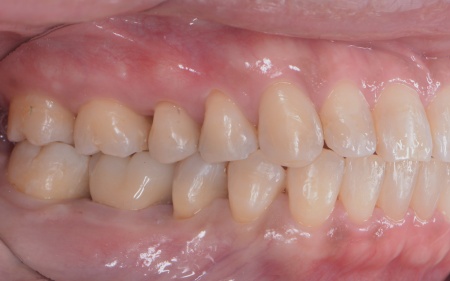

とくに上の左右奥歯には、矯正用ミニインプラント(矯正治療専用の小さなネジ)を埋入し、奥歯を歯茎の方向に押し下げる「圧下」という治療を行っています。これにより開咬が解消され、前歯でしっかり噛めるようになりました。

また、治療によって奥歯に過度な力がかかりにくくなったため、舌の動きをスムーズにしつつ歯磨きなどのセルフケアがしやすくなるよう、下顎隆起の除去を行いました。

最後に、右下奥歯に装着されていた銀の詰め物を外し、強度と審美性に優れた白い被せ物であるジルコニアセラミッククラウンを装着します。見た目や噛み合わせ、使用感などに問題がないことを確認し、治療を終了しました。